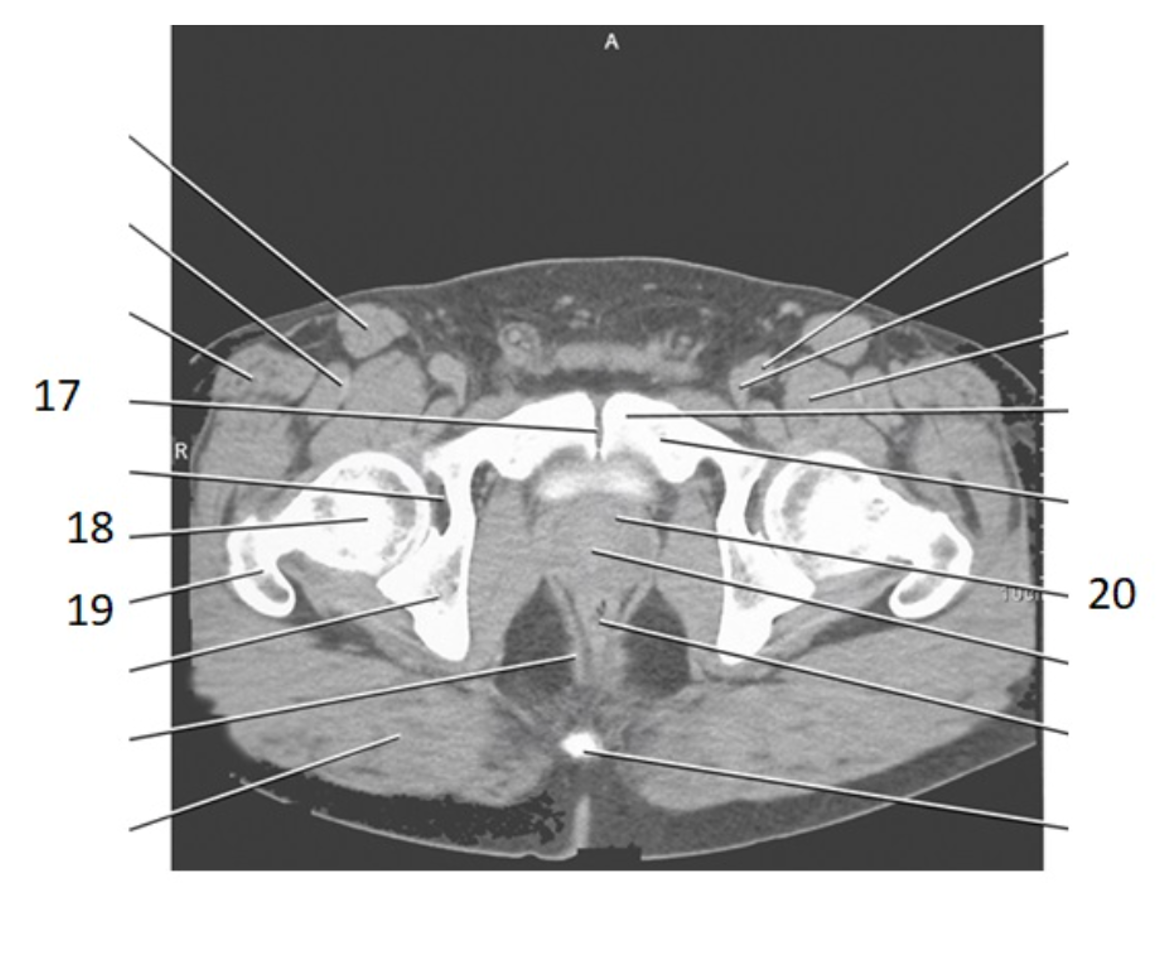

17

pubic bone

pubic symphysis

19

greater trochanter

20

prostate